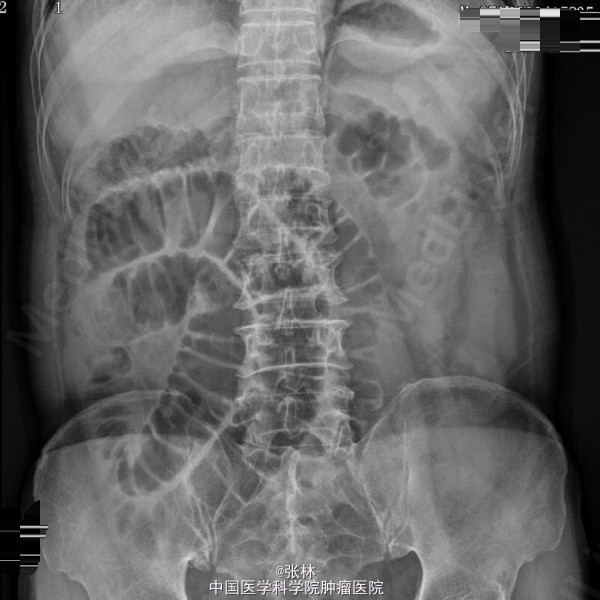

男性,72岁。 主诉:突发腹痛、腹胀伴呕吐1天。 现病史:患者1天前无诱因感全腹部疼痛,呈阵发性绞痛,无放射痛,疼痛开始不剧,伴有畏寒,呕吐胃内容物1次,量约30ml。遂到我院门诊就诊,考虑为急性胃肠炎,予抗炎、解痉护胃等支持治疗,症状未见好转,并进行性加重而入住我科。 专科检查:全腹稍胀,未见肠型及蠕动波,无上腹搏动。腹软,中下轻压痛,无反跳痛。全腹未及肿块,肠鸣音活跃,7次/分。 术中所见:探查见异物位于回肠距回盲部约50cm,大小约8*3*2cm,堵塞肠管,近端肠管充血水肿明显,肠管扩张最大处直径约8cm,未见浆膜层破裂损伤等,系膜无扭转,有少许渗液,探查全部小肠未及肿物腹腔内可见中等量黄色积液,稍浑浊,网膜及腹膜有少量脓苔。洗净腹腔内积液,于肿物边缘对肠系膜缘纵行切开约2cm,取出异物,为半个大小约8*3*2cm的冬菇。